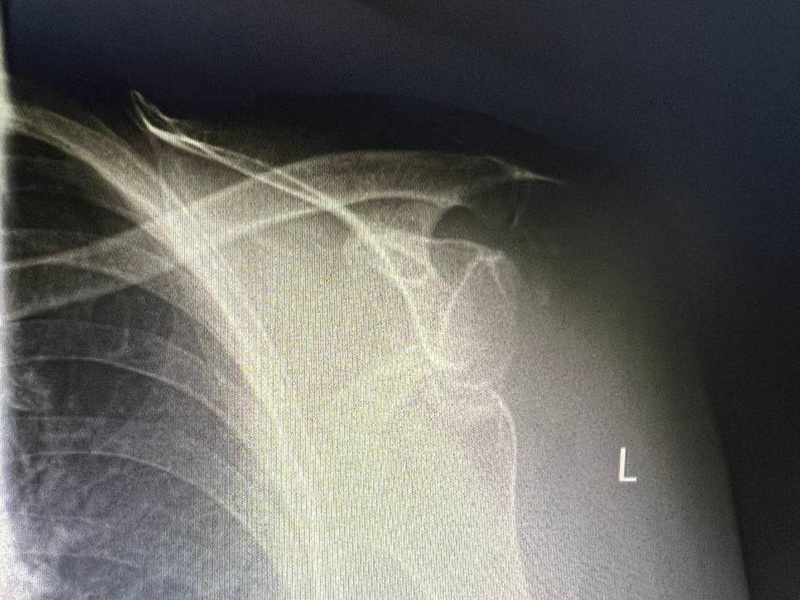

Остеосинтез плеча вивих ДО-ПІСЛЯ: